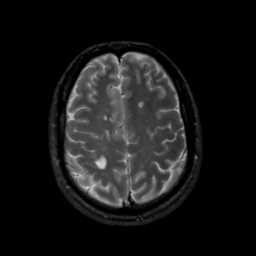

MR Study #16, June 23, 1991 -- Slice #38